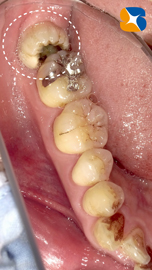

レントゲンからも大きな虫歯を確認。本日、昼休み中にインプラント手術があります。それが終わり次第抜歯を行うことにしました。

歯の上半分が虫歯のため、崩壊していましたので難しい抜歯になりましたが、無事に終えることができました。